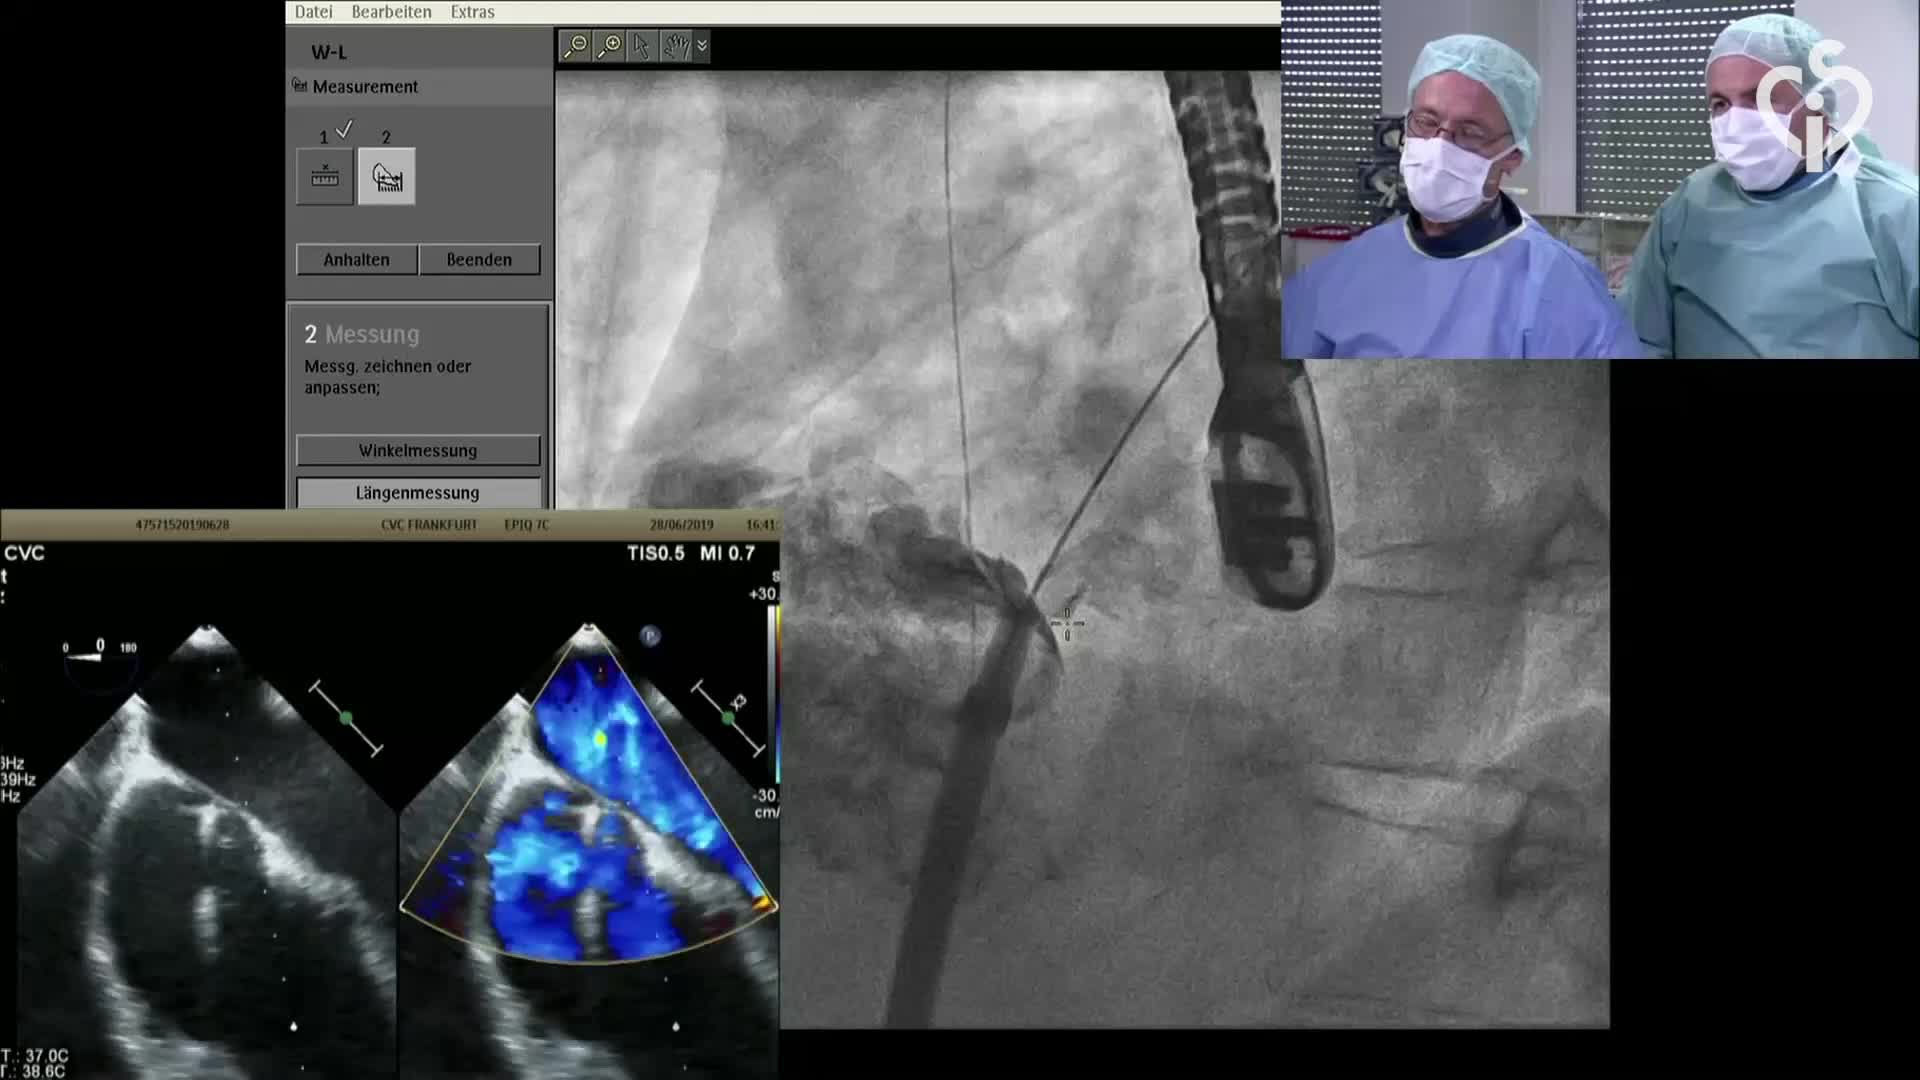

CSI CATHLAB LIVE - VSD CLOSURE WITH THE NEW OCCLUTECH PMVSD OCCLUDER (ANTEGRADE APPROACH)